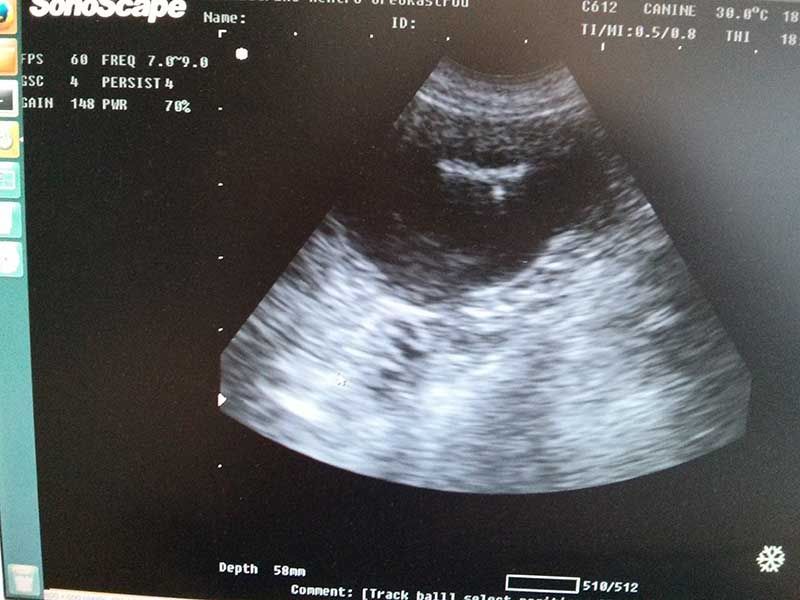

Μαιευτικό τμήμα:

Διάγνωση εγκυμοσύνης, Δυστοκία, Χρονισμός καισαρικής τομής, Διερεύνιση υπογεννητικότητας, Πυομήτρα, Διαταραχές μαστών, Νεοπλασίες γεννητικού – Μαστεκτομές